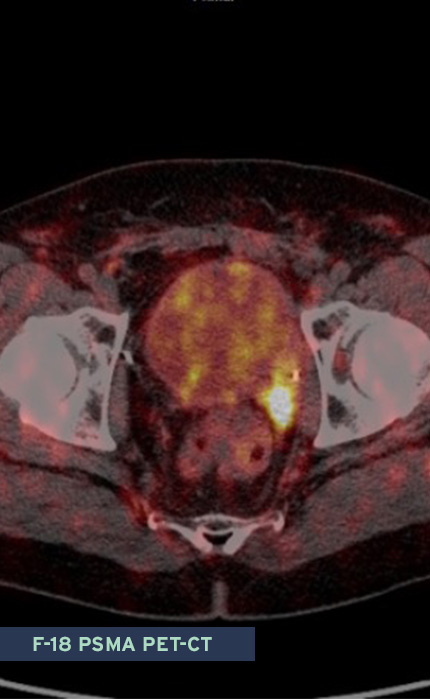

Die Gemeinschaftspraxis bietet ein breites Spektrum von radiologischen und nuklearmedizinischen Untersuchungsverfahren an, welche von der Detektion eines Prostatakarzinoms (multiparametrische Magentresonanztomographie), über die Ausbreitungsdiagnostik bei einem diagnostizierten Prostatakarzinom (Computertomographie, Magnetresonanztomographie, Röntgen) bis zur Ausbreitungs- und Rezidivdiagnostik mittels Knochenszintigraphie und PSMA-PET-CT reichen. Auch bei Schmerzen durch ein in die Knochen metastasiertes, fortgeschrittenes Prostatakarzinom können wir Ihnen mittels Schmerztherapie helfen.